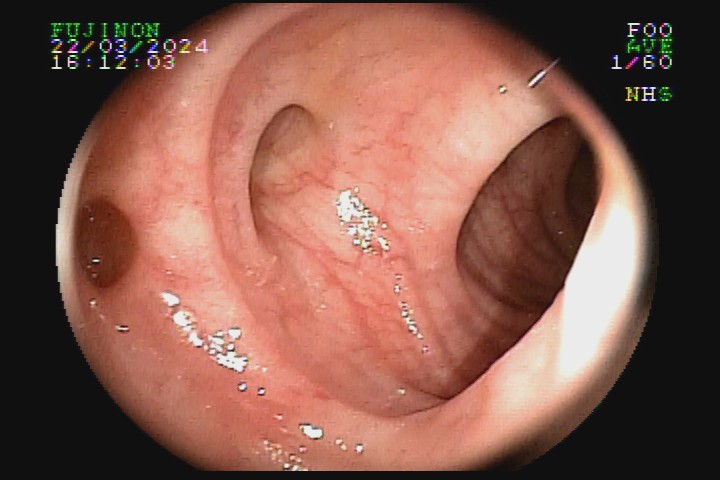

A diverticulose é uma doença adquirida, frequente entre pessoas mais idosas. Acredita-se que tenha como principal fator etiológico hábitos dietéticos relacionados com o refinamento da dieta industrializada. Pode ter uma evolução benigna por toda a vida e ser totalmente assintomática, mas pode também caracterizar-se como doença de sinais e sintomas agressivvos, com considerável morbidade e mortalidade devido às suas principais complicações: inflamação e sangramento.

A diverticulose cólica é consequência da herniação da mucosa do intestino grosso por entre as fibras musculares da parede intestinal. A diverticulose do cólon esquerdo complica mais com inflamação, e a diverticulose do cólon direito complica mais com sangramento.